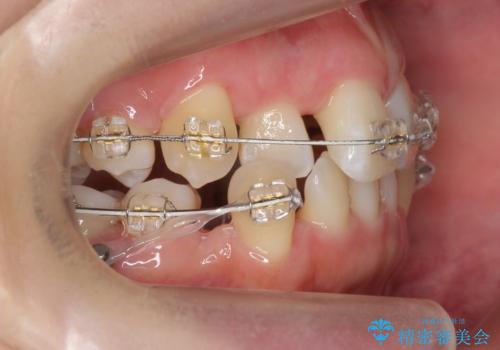

- 矯正装置

- 審美装置

- 2年3ヶ月

- 10-30回

小臼歯を4本抜歯しています。